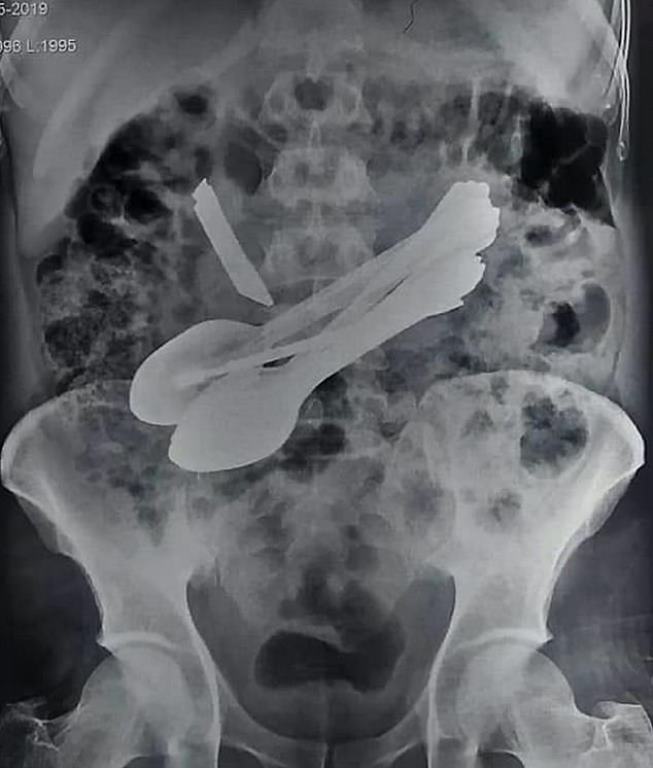

La prueba de rayos X reveló cucharas en su estómago, pero estas solo eran la punta del iceberg. Los médicos también vieron un cuchillo que parecía perforar el estómago del paciente.

Los médicos quedaron atónitos al descubrir un cuchillo, ocho cucharas y un destornillador dentro de un hombre de 35 años, que se quejaba de un dolor de estómago insoportable.

“Había un cuchillo, ocho cucharas, dos destornilladores y dos cepillos de dientes adentro mientras continuamos operando su estómago”.

Una barra de metal también fue recuperada de su estómago. Se entiende que el hombre de 35 años sufría un trastorno psiquiátrico que lo llevó a comer objetos.